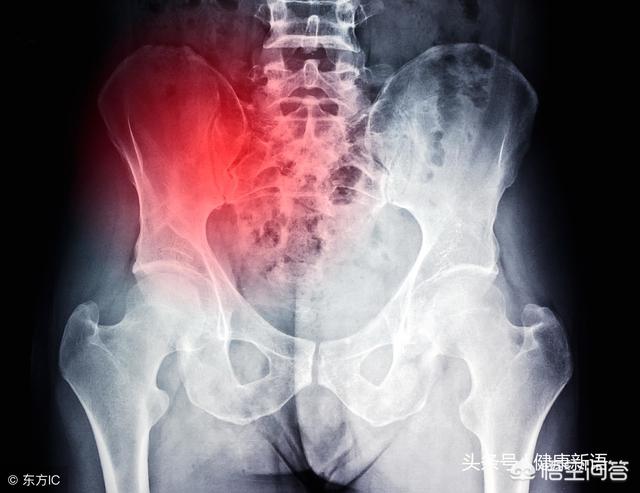

左侧腰部下方疼痛,如果咳嗽打喷嚏会痛,负重的时候会疼痛,痛感在腰部的深层,下腰部按压会有相应的痛感,拍片的时候可以发现L4-5或者L5-S1椎间盘突出存在,这俩椎间盘突出硬膜囊受压,都在下腰部疼痛。